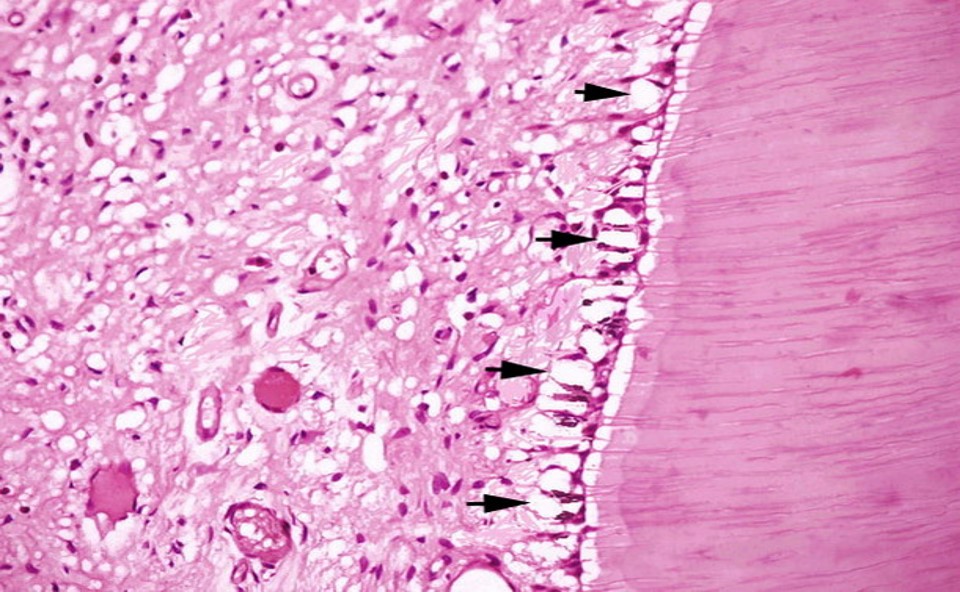

镜下:成牙本质细胞体积变小,细胞间水泡挤压成牙本质细胞呈稻草束状(图8.2-1)。

图8.2-1 成牙本质细胞空泡性变